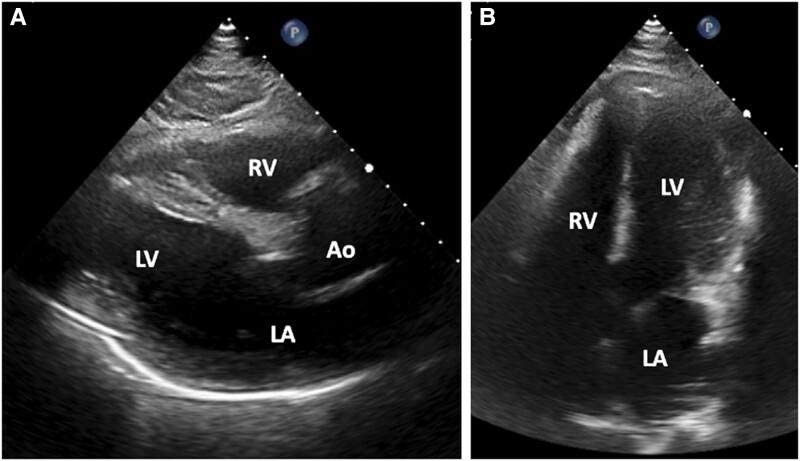

We describe a case of contained rupture of a large left ventricular aneurysm (LVA) presenting with syncope in a 60-year-old male with late presentation myocardial infarction (MI) 6 weeks prior on home triple antithrombotic therapy (TAT). Urgent pericardiocentesis along with imaging techniques including ultrasound, computed tomography angiography (CTA), and cardiac magnetic resonance imaging (MRI) were used for initial diagnosis. Definitive treatment was achieved with excision and repair of the LVA with return to prior functional status 1 month after intervention.